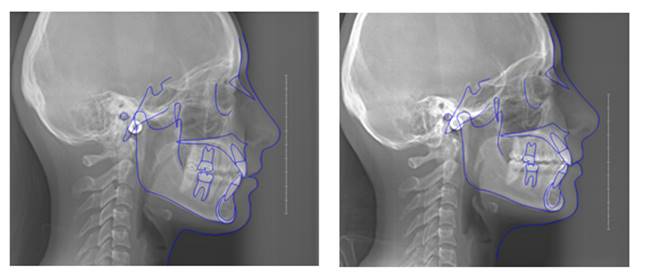

Methods: The clinical examination included extra-oral and intra-oral photographs, panoramic radiographic, lateral cephalometric, stone casts, and upper and lower arch analysis obtained from ClinCheck 3.0.The treatment planning was resolved the crowding in both upper and lower arches and the severe rotation of 33 tooth (46°) using Invisalign system as well as the canine and molar relationship, dental verticalization, adequate over jet, overbite and dental midline using the same system. The duration of the treatment was approximately eight months.

Results: In Post-treatment extra oralphotographs, no significant changes were observed at the end of the treatment. Intraoral photographs showed an important and notable improved aesthetics. The canine relationship improved slightly and molar Class Irelationship was maintained. An increase in transverse diameter was observed at the level of first premolars, second premolars and first molars. The overbite was improved. The crowding and the severe canine rotation were corrected. No obvious root resorption was radiographically evident and slight cephalometric changes.